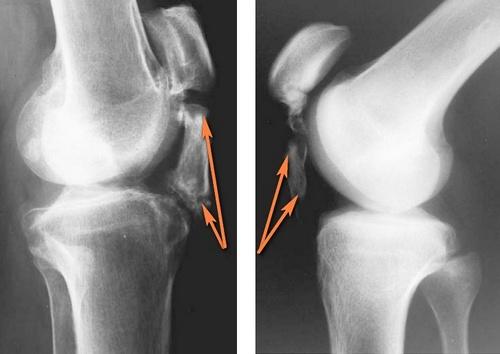

На раннем этапе диагностики врач выполняет осмотр и пальпацию поврежденной области. Обязательно следует провести дифференциальную диагностику тендинита с другими аномалиями. Чтобы уточнить диагноз, проводят такие процедуры:

- Рентгенография – позволяет диагностировать последнюю стадию недуга, которая спровоцирована скоплением солей. Также процедура помогает обнаружить бурсит и артрит.

На фото рентгеновский снимок для диагностики тендинита